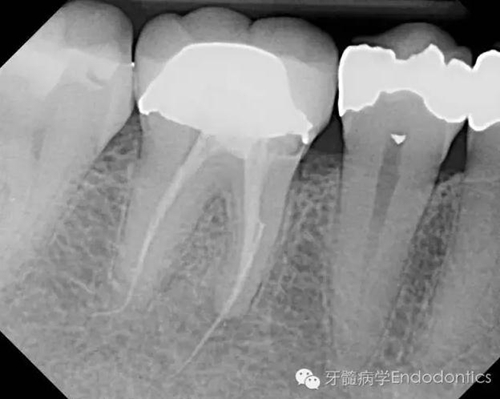

患者因右下第一前磨牙劇烈疼痛、腫脹來(lái)診,自訴2年前該牙行根管治療,突發(fā)劇痛。X線示患牙已行根管治療并超填。患牙診斷為已行根管治療合并急性根尖周膿腫。一些牙醫(yī)和牙髓病專科可能會(huì)直接采取根尖手術(shù)治療患牙,而我認(rèn)為手術(shù)是最終手段,尤其對(duì)于該病例。

圖1.術(shù)前X線片(a)

圖2.術(shù)前X線片(b)